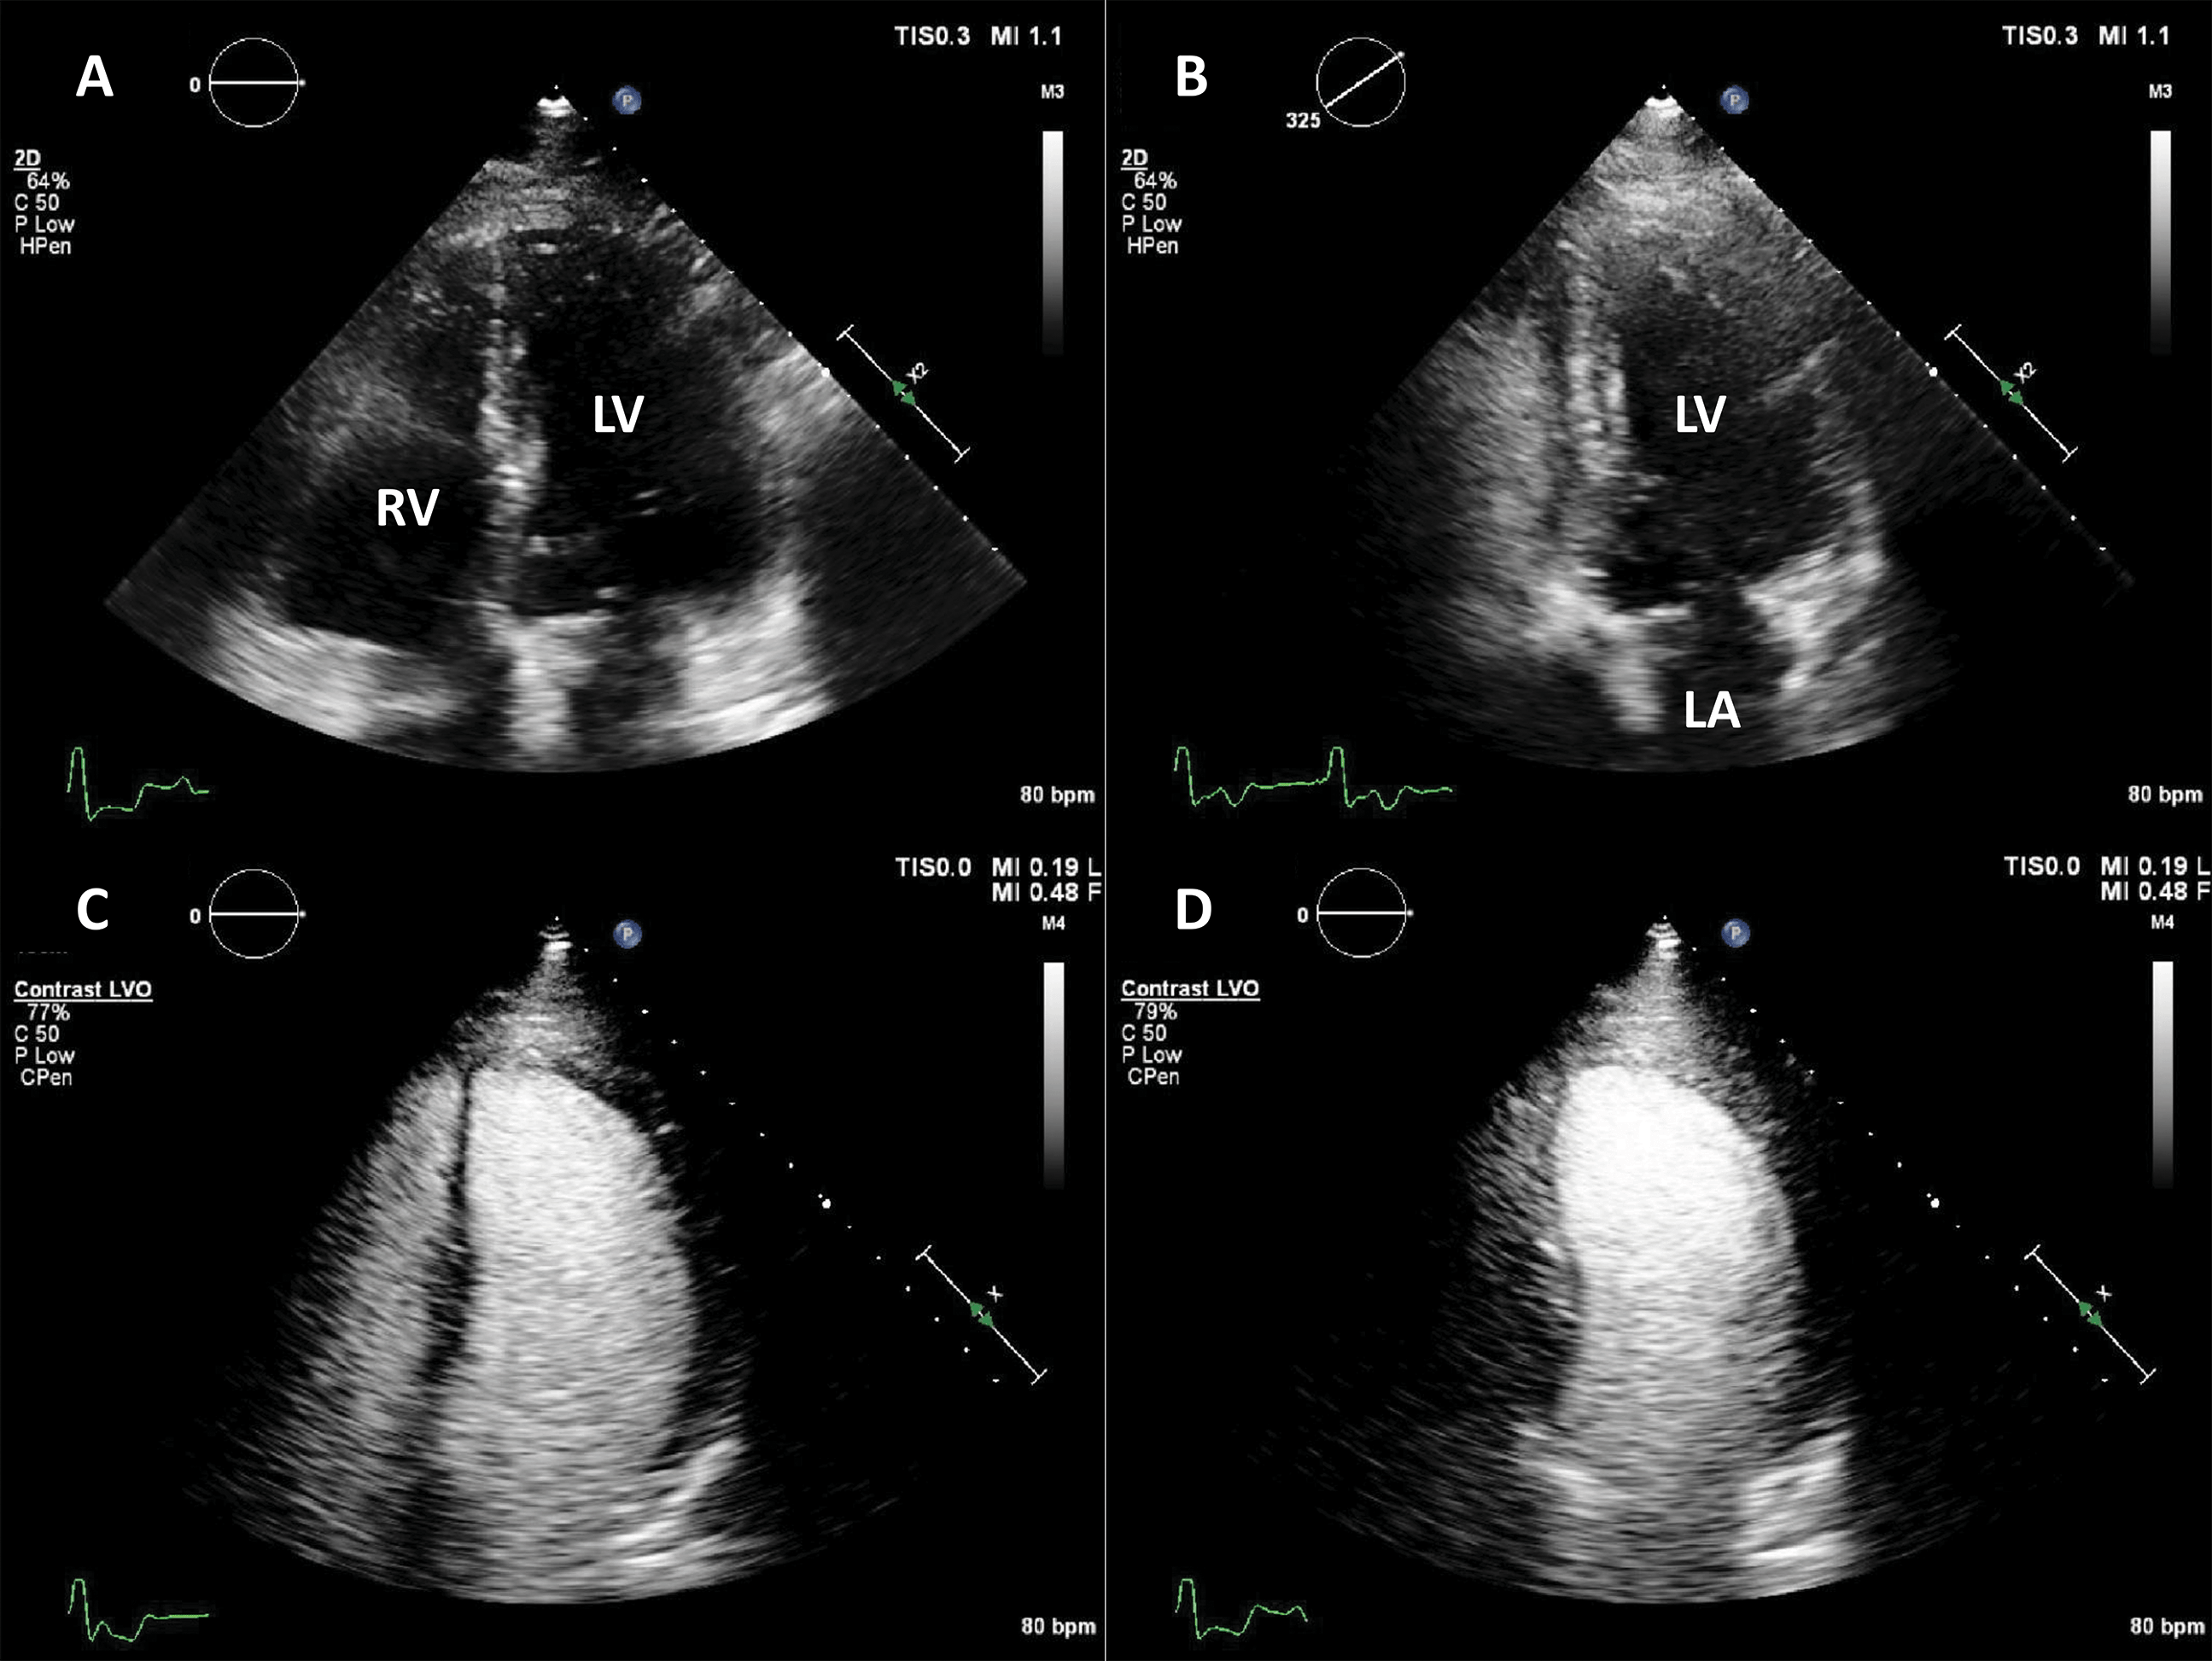

The addition of UEA during stress echocardiography protocols is usually achieved through an LVO application with low-MI harmonic imaging (Fig. 7, Video 6). The result is an increase in the likelihood of a diagnostic test, a better visualization of all myocardial segments, study quality and reader confidence, as compared to invasive or non-invasive reference [40, 41, 42, 43]. The addition of UEA to non-enhanced studies resulted in a better agreement with coronary angiography, even in patients with intermediate coronary lesions [44]. Of course, the use of LVO in stress echo has the largest impact in patients with suboptimal image [45]. Nevertheless, contrast-enhanced ultrasound also improves the wall motion score and detection of regional wall motion abnormalities in patients with adequate image quality [46]. Contrast-enhanced dobutamine stress echocardiography provided adequate risk stratification in patients with increased cardiovascular risk due to obesity or suspected coronary artery disease [47, 48, 49].

Fig. 7.Microbubble enhanced stress echocardiography. Baseline non-enhanced images are recorded in apical 4 and 2 chambers (A,B), demonstrating insufficient delineation of the endocardial borders; With contrast (C,D) the LV contours become clearly visible. Source: personal collection.

In patients with incomplete visualization of at least 2 contiguous segments contrast should be used for stress echocardiography. In patients with adequate image quality, contrast could be used to assess the myocardial perfusion, in addition to wall motion [7, 13].